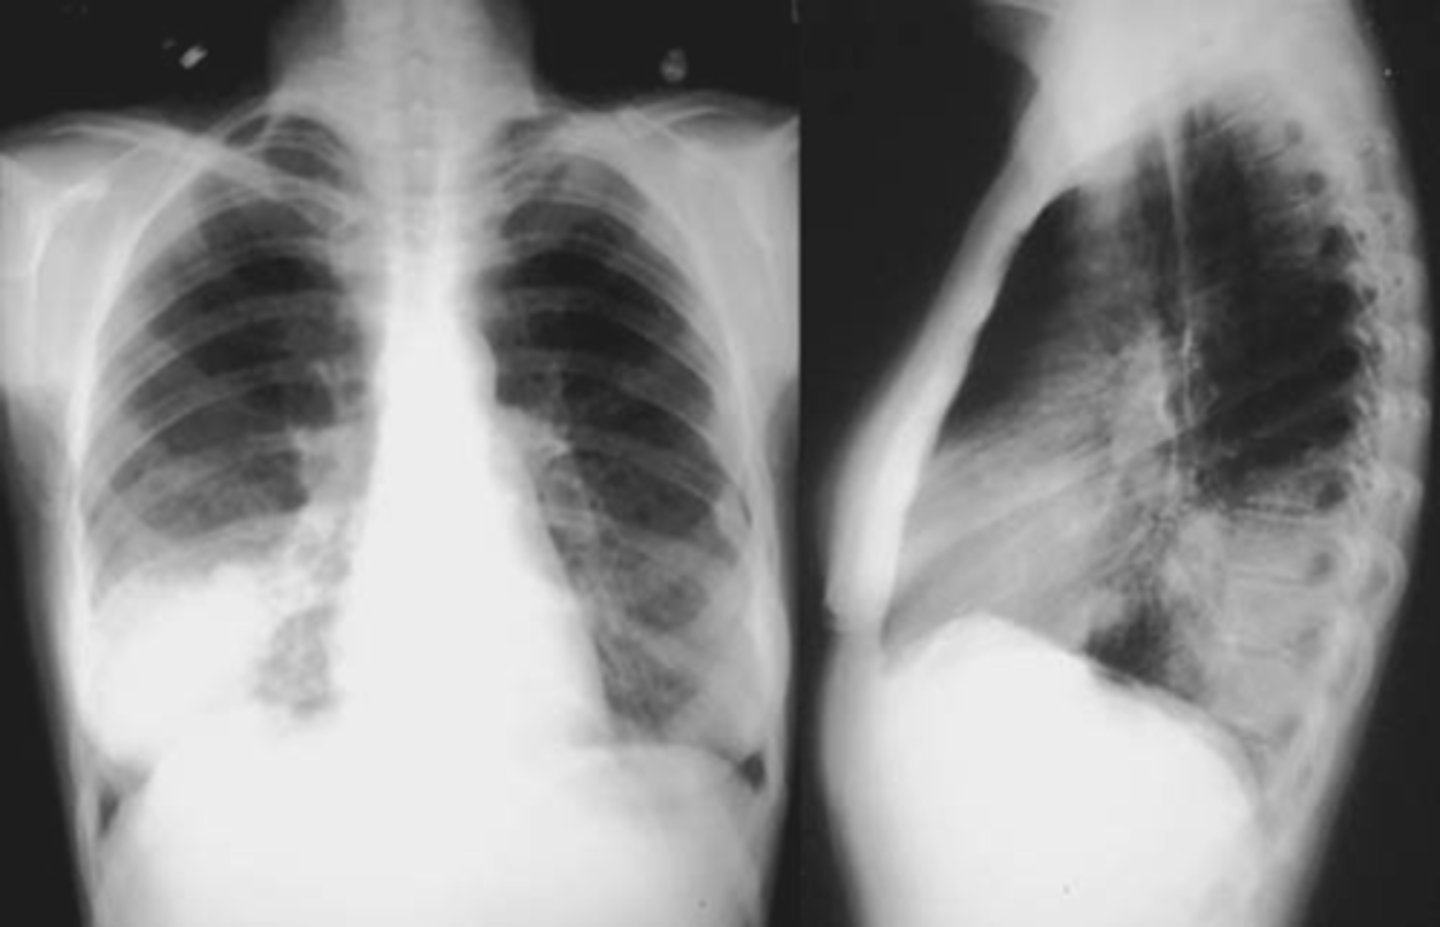

community acquired pneumonia

Silhouette sign

spine sign

CAP- interstitial

CAP- round